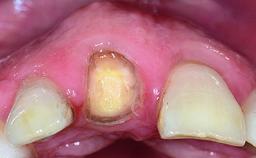

A healthy 37-year-old female patient was referred for a consultation on the replacement of missing tooth 21 with an implant-supported restoration. She stated that several years previously the tooth had been traumatically avulsed following a motor vehicle accident. The tooth was replaced with a three-unit fixed partial denture (FPD) immediately afterwards. Over time, she became disillusioned with the FPD and looked for a different option, including orthodontic therapy. She presented still in her orthodontic appliances, with the pontic sectioned free from the FPD but attached to the archwire. Her orthodontist felt that orthodontic treatment had been successfully completed, but nevertheless referred her before removing the appliances in case adjustments were necessary.

Soft Tissue Anatomy Intact Defective

Bone Volume Horizontally and vertically sufficient Horizontally deficient Deficient vertically or deficient vertically AND horizontally